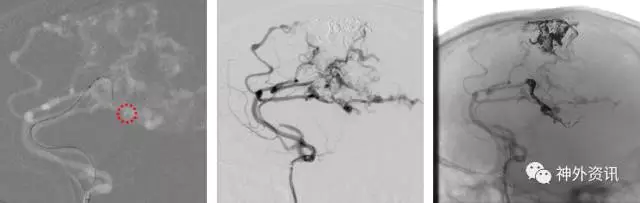

(3D血管融合:左侧额颞顶部巨大AVM,大小约10.4*6.7*5.7cm)

(治疗中,ENVOY DA导引导管置于左侧大脑前动脉A1段)

(SONIC 导管顺利超选至畸形血管巢,并且拔管顺利)

(挑战:终末血管供血,超选距离遥远,途经血管迂曲,选择使用Envoy DA)

(Envoy DA导引导管—右侧大脑前动脉A1段)

(成功超选,栓塞后拔管顺利)

栓塞术后畸形团少量残留,静脉引流通畅,后2期行手术切除,术后复查脑血管造影畸形团未见明显残留。